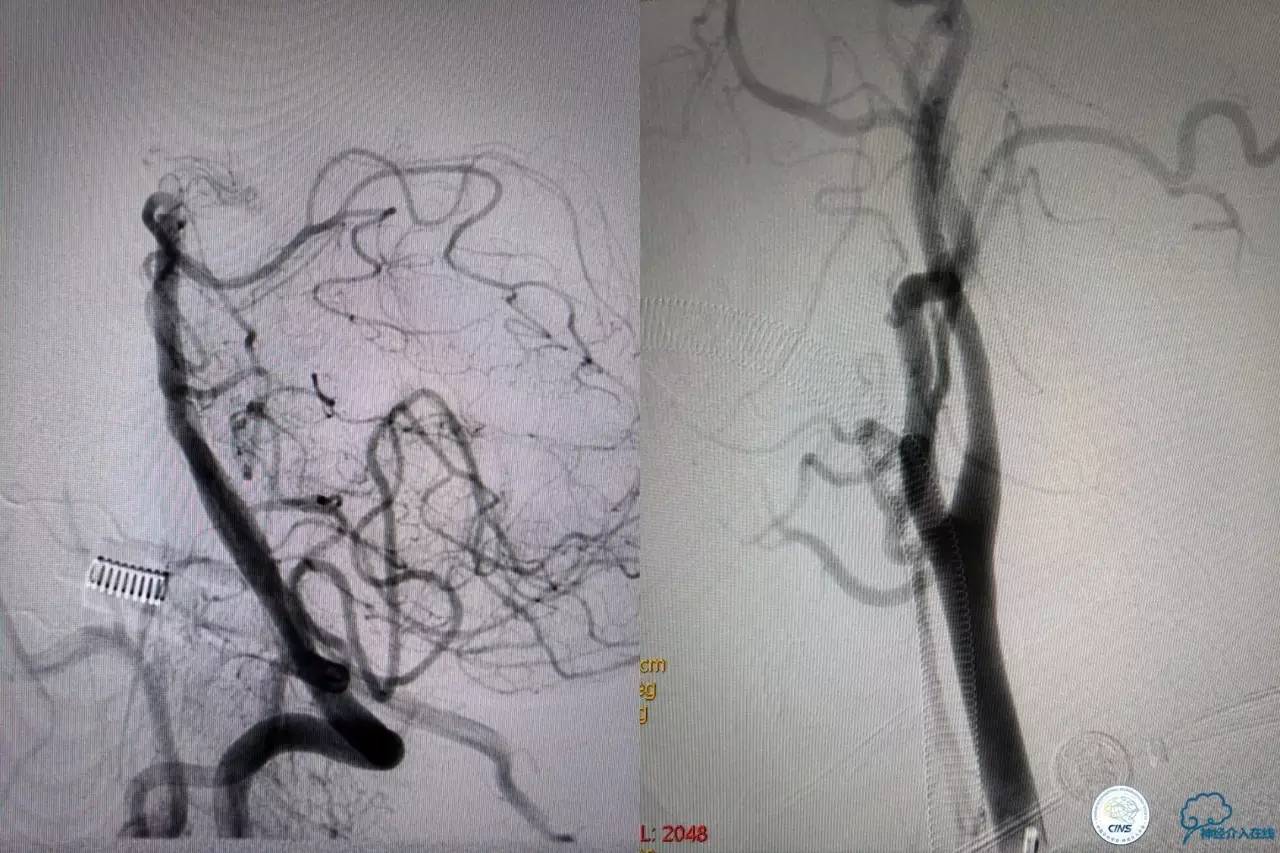

造影结果:右侧颈总动脉远端闭塞,前交通动脉开放,代偿方式:左侧颈内动脉→左侧大脑前动脉A1→前交通动脉→右侧大脑前动脉A1(反向)→右侧大脑中动脉供血区代偿。双侧大脑后动脉、右侧小脑上动脉及基底动脉顶端未见显影。

结合病史,体征及影像学,考虑患者本次发病为基底动脉尖急性闭塞,发病机制:栓塞?右侧颈总动脉慢性闭塞?非责任血管,且代偿良好,暂时不需处理!

6F导引导管到位至RV2远端,rebar-18微导管及transand微导丝至右侧大脑后动脉P1远端。

solitaireAB4-20mm支架取栓。

基底动脉顶端仍有大量血栓,双侧大脑后动脉未见显影,双侧小脑上动脉再通。再次取栓?还是动脉溶栓?

决定导管内给予替罗非班6ml,复查造影BA顶端仍闭塞,第二次取栓。